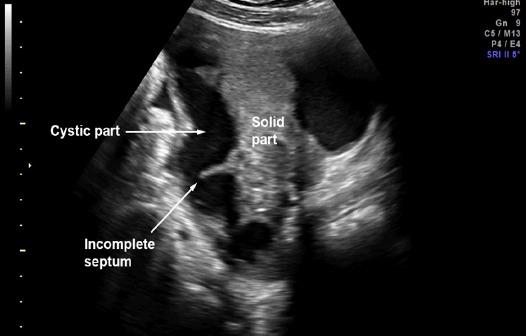

Objective: To evaluate diagnostic performance of IOTA simple rules plus pattern recognition in predicting tubal cancer. Methods: Secondary analysis was performed on prospective database of our IOTA project. The patients recruited in the project were those who were scheduled for pelvic surgery due to adnexal masses. The patients underwent ultrasound examinations within 24 hours before surgery. On ultrasound examination, the masses were evaluated using the well-established IOTA simple rules plus pattern recognition (sausage-shaped appearance, incomplete septum, visible ipsilateral ovaries) to predict tubal cancer. The gold standard diagnosis was based on histological findings or operative findings. Results: A total of 482 patients, including 15 cases of tubal cancer, were evaluated by ultrasound preoperatively. The IOTA simple rules plus pattern recognition gave a sensitivity of 86.7% (13 in 15) and specificity of 97.4%. Sausage-shaped appearance was identified in nearly all cases (14 in 15). Incomplete septa and normal ovaries could be identified in 33.3% and 40%, respectively. Conclusion: IOTA simple rules plus pattern recognition is relatively effective in predicting tubal cancer. Thus, we propose the simple scheme in diagnosis of tubal cancer as follows. First of all, the adnexal masses are evaluated with IOTA simple rules. If the B-rules could be applied, tubal cancer is reliably excluded. If the M-rules could be applied or the result is inconclusive, careful delineation of the mass with pattern recognition should be performed.

https://cdn.ncbi.nlm.nih.gov/pmc/blobs/3128/5773785/ddf549a18615/APJCP-18-3011-g001.jpg